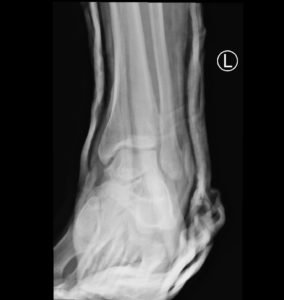

Subtalar dislocation is an unusual form of joint injury from high-energy trauma or athletic injuries. This case report describes a 22-year-old male who presented to the emergency department with left ankle pain after falling from his bicycle. Examination revealed significant deformity of the left foot and ankle. The foot pointed medially, and the bottom portions of the tibia and fibula were visible with the overlying skin intact. Radiographs confirmed left medial subtalar dislocation. There was no neurovascular compromise of the foot. The dislocation was successfully reduced under procedural sedation and the patient’s left leg was placed in a splint. He underwent post-reduction imaging and was instructed to remain non-weight-bearing and to follow up with orthopedics to discuss further management. The purpose of this report is to describe a case of a closed, medial subtalar dislocation and the approach to management.